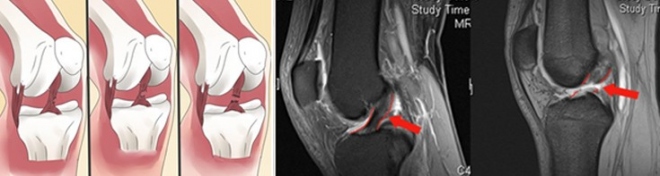

Η παρακέντηση του γόνατος αντί για ύδραρθρο (υγρό) θα δώσει πάντα αίμαρθρο, δηλαδή αίμα, σε αρκετή συνήθως ποσότητα, γιατί ο κομμένος χιαστός έχει αγγεία. Δεν είναι σαν τον μηνίσκο που στερείται αγγείων.

Η κλινική διάγνωση της ρήξης σήμερα επιβεβαιώνεται με μαγνητική τομογραφία.

Εάν η ρήξη στην απεικόνιση της μαγνητικής μοιάζει μερική και εάν το γόνατο δεν «φεύγει» πολύ, αλλά είναι κλινικά σταθερό, μπορεί κανείς να δοκιμάσει συντηρητική αντιμετώπιση. Αυτό εξαρτάται και από την ηλικία. Σε νεώτερα άτομα η πρόσθια αστάθεια που προκαλείται από έλλειψη του προσθίου χιαστού, προκαλεί προοδευτικά ραιβοποίηση του γόνατος και αρθρίτιδα και συνεπώς πρέπει ν΄ αντιμετωπίζεται χειρουργικά.